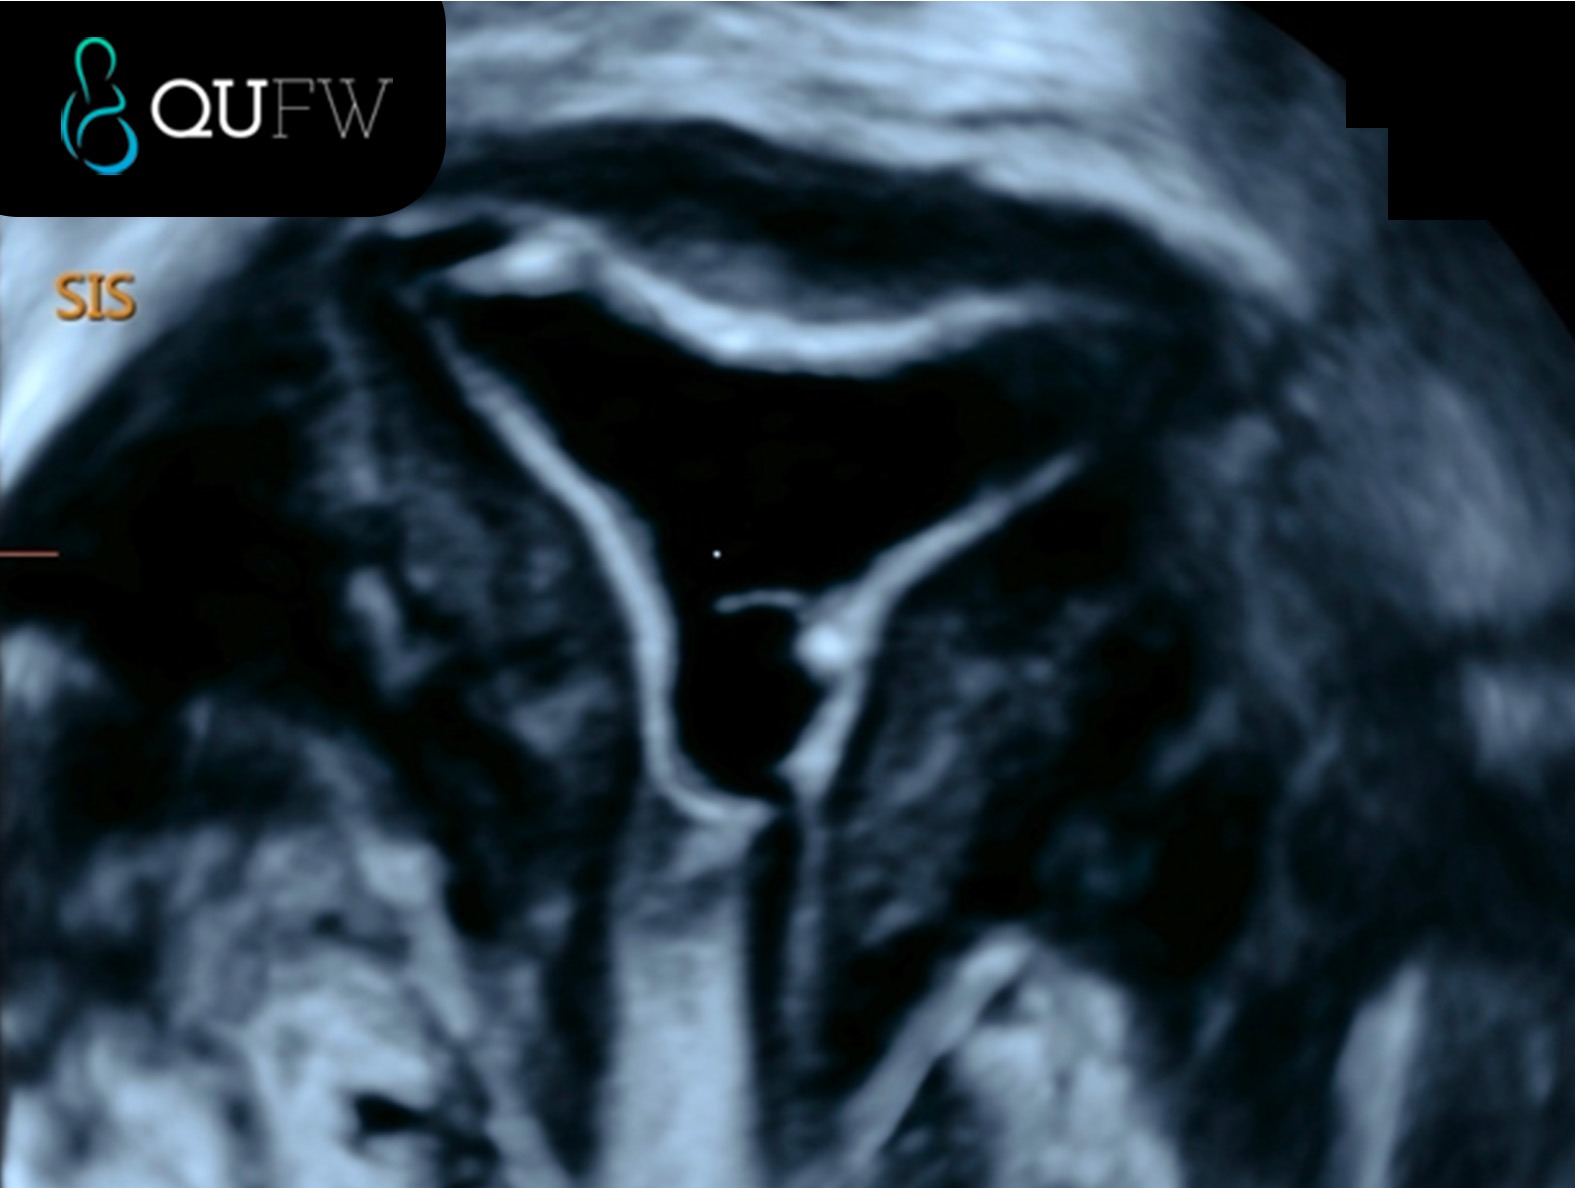

Saline Infusion Sonography (SIS) showing a 3D coronal reconstructed image of a submucosal fibroid

Saline Infusion Sonography (SIS) showing the endometrial cavity in the coronal plane